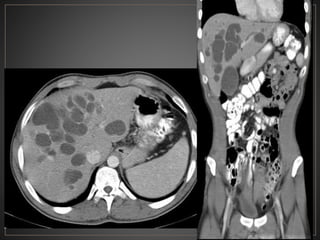

CPRE: Dilataciones saculares de CBIH. TC: Simple:Áreas redondas, hipointensas en topografía de CBIH. Contraste: Signo del punteado central. RM: T2: Espacios quísticos hiperdensos

• #47 Axial ventana tejidos blando fase portal, se observan multiples imágenes de morfología ovalada, de bordes definidos, hipodensa, correpondiente a quistes intrahepaticos y un quiste grande extrahepatico - tipo IVa

• #48 V-Dilataciones multiples o simples intrahepaticos (enfermedad de Caroli)

• #53 El CT axial con contraste muestra una dilatación masiva de los conductos biliares intrahepáticos. punto "central" o "excéntrico" en muchas de las estructuras quísticas, que representan las venas portas, un clásico hallazgo de imágenes en la enfermedad de Caroli.

• #54 CT contrastada fase portal, observan imágenes hipointensas con un centro hiperintenso en relación a dilatación sacular árbol biliar (central dot)